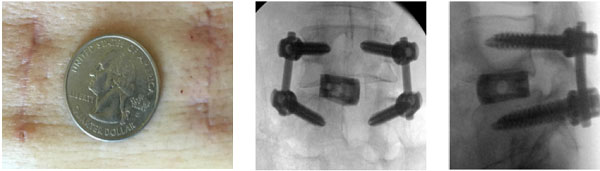

– Đường mổ nhỏ, sẹo mổ thẩm mỹ

Có nhiều kỹ thuật mổ cột sống ít xâm lấn đang được áp dụng tại khoa Chấn thương chỉnh hình và cột sống – Bệnh viện Bạch mai để điều trị một số bệnh lý cột sống như:

– Chấn thương cột sống ngực – thắt lưng

– Hẹp ống sống thắt lưng

– Trượt đốt sống thắt lưng cùng

– Thoát vị đĩa đệm cột sống thắt lưng